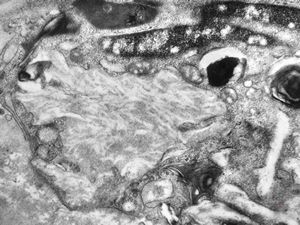

F, 25y. | metachromatic leukodystrophy … n. suralis